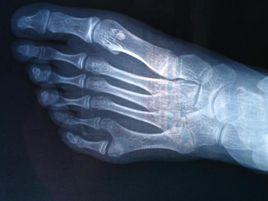

2008年10月30日凌晨3時許,廣東省雷州市一產婦在該市婦幼保健院育出一個八趾男嬰。該嬰呱呱落地,體重6.8斤。之後,院方對其檢查身體,因膽黃素偏高須留院護理,11月1日送駐地醫院兒科觀察,直至5日出院並隨父母回到南興鎮圩。 6日中午,記者趕到南興鎮圩採訪看到,嬰兒活潑可愛,腳部彎向小腿內側,左右兩腳分別長了八個腳趾,十分整齊。從外形看,散開的八個腳趾就像一朵雞冠花。記者還發現,該嬰兒兩手都長有五個指頭,卻沒有大拇指。

8歲的小玉,因為買不到合腳的鞋子赴重慶就醫。在重慶醫科大學附屬兒童醫院,醫生讓小玉脫掉鞋襪後發現,原來小玉家長說孩子無法買到合適的鞋子,竟是因為小玉雙腳一共有15根腳趾。12日,記者在兒童醫院見到了小玉。